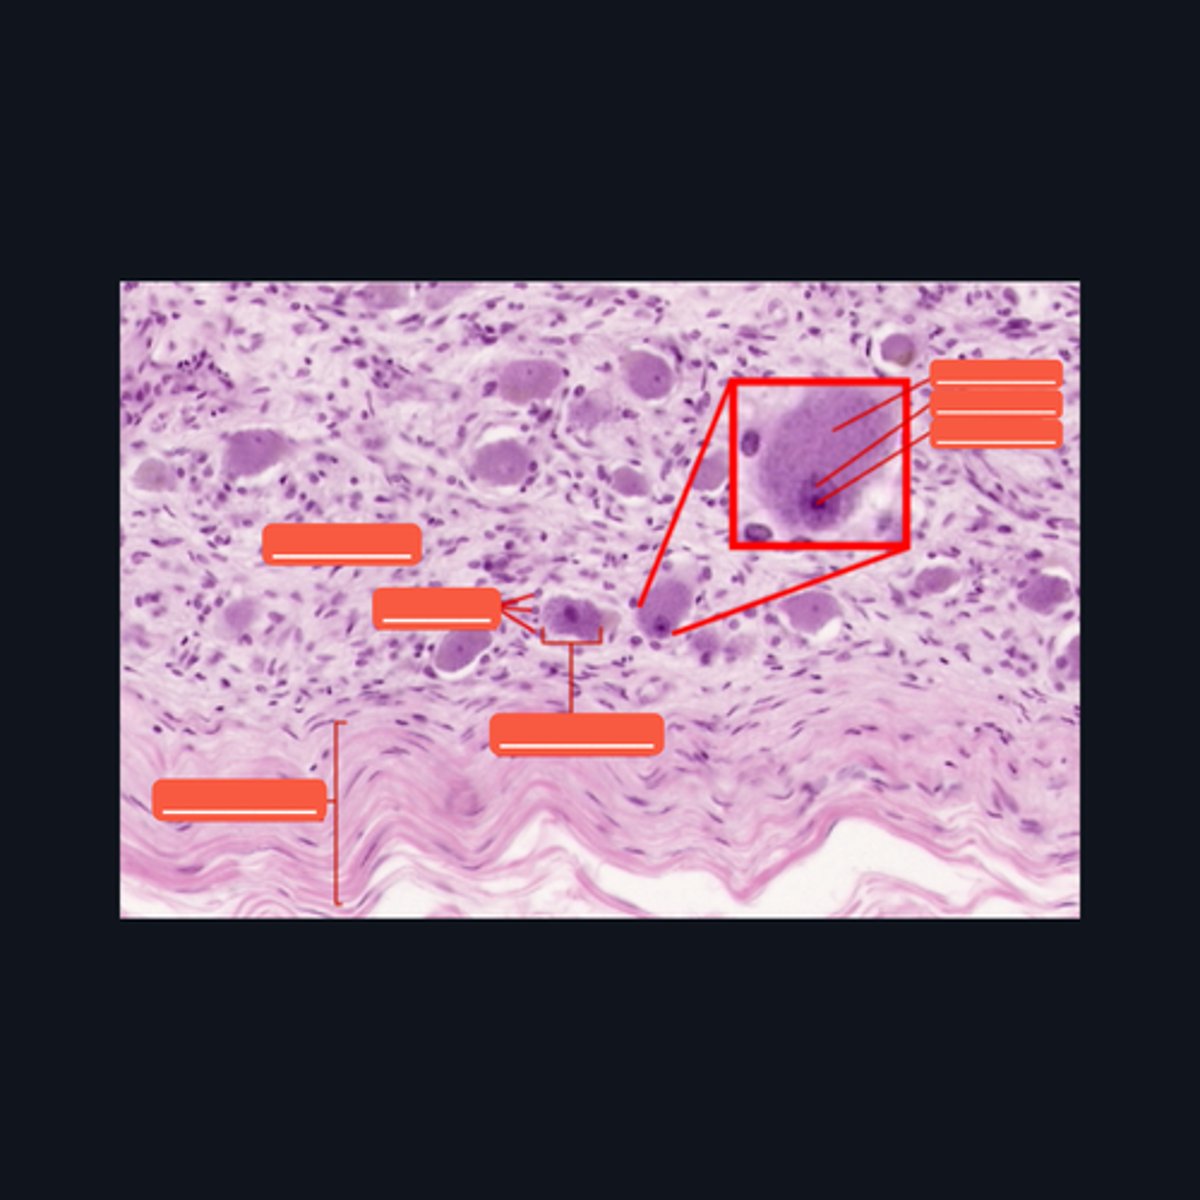

Mucosa, Submucosa, Muscularis Externa

Identify the histologic layers of the digestive tract

(1) Visceral Efferent Neuerons/ Autonomic Ganglion Cells

(2) Meissner's Plexus and Auerbach's Plexus

Cells from the division of the nervous system that innervates this specimen are made up of (1)_______, and whose cell bodies and fibers form (2) two ganglionated plexuses named: _______ and ________.

Submucosa

Identify the pointed histologic layer of the digestive tract

Muscularis Externa

Identify the pointed histologic layer of the digestive tract

Serosa

Identify the pointed histologic layer of the digestive tract

Meissner's corpuscle, Lamellar cells, and Capsule

Identify each pointed structures.

Pacinian corpuscle, Supporting cells, Axon

Identify the pointed structures.